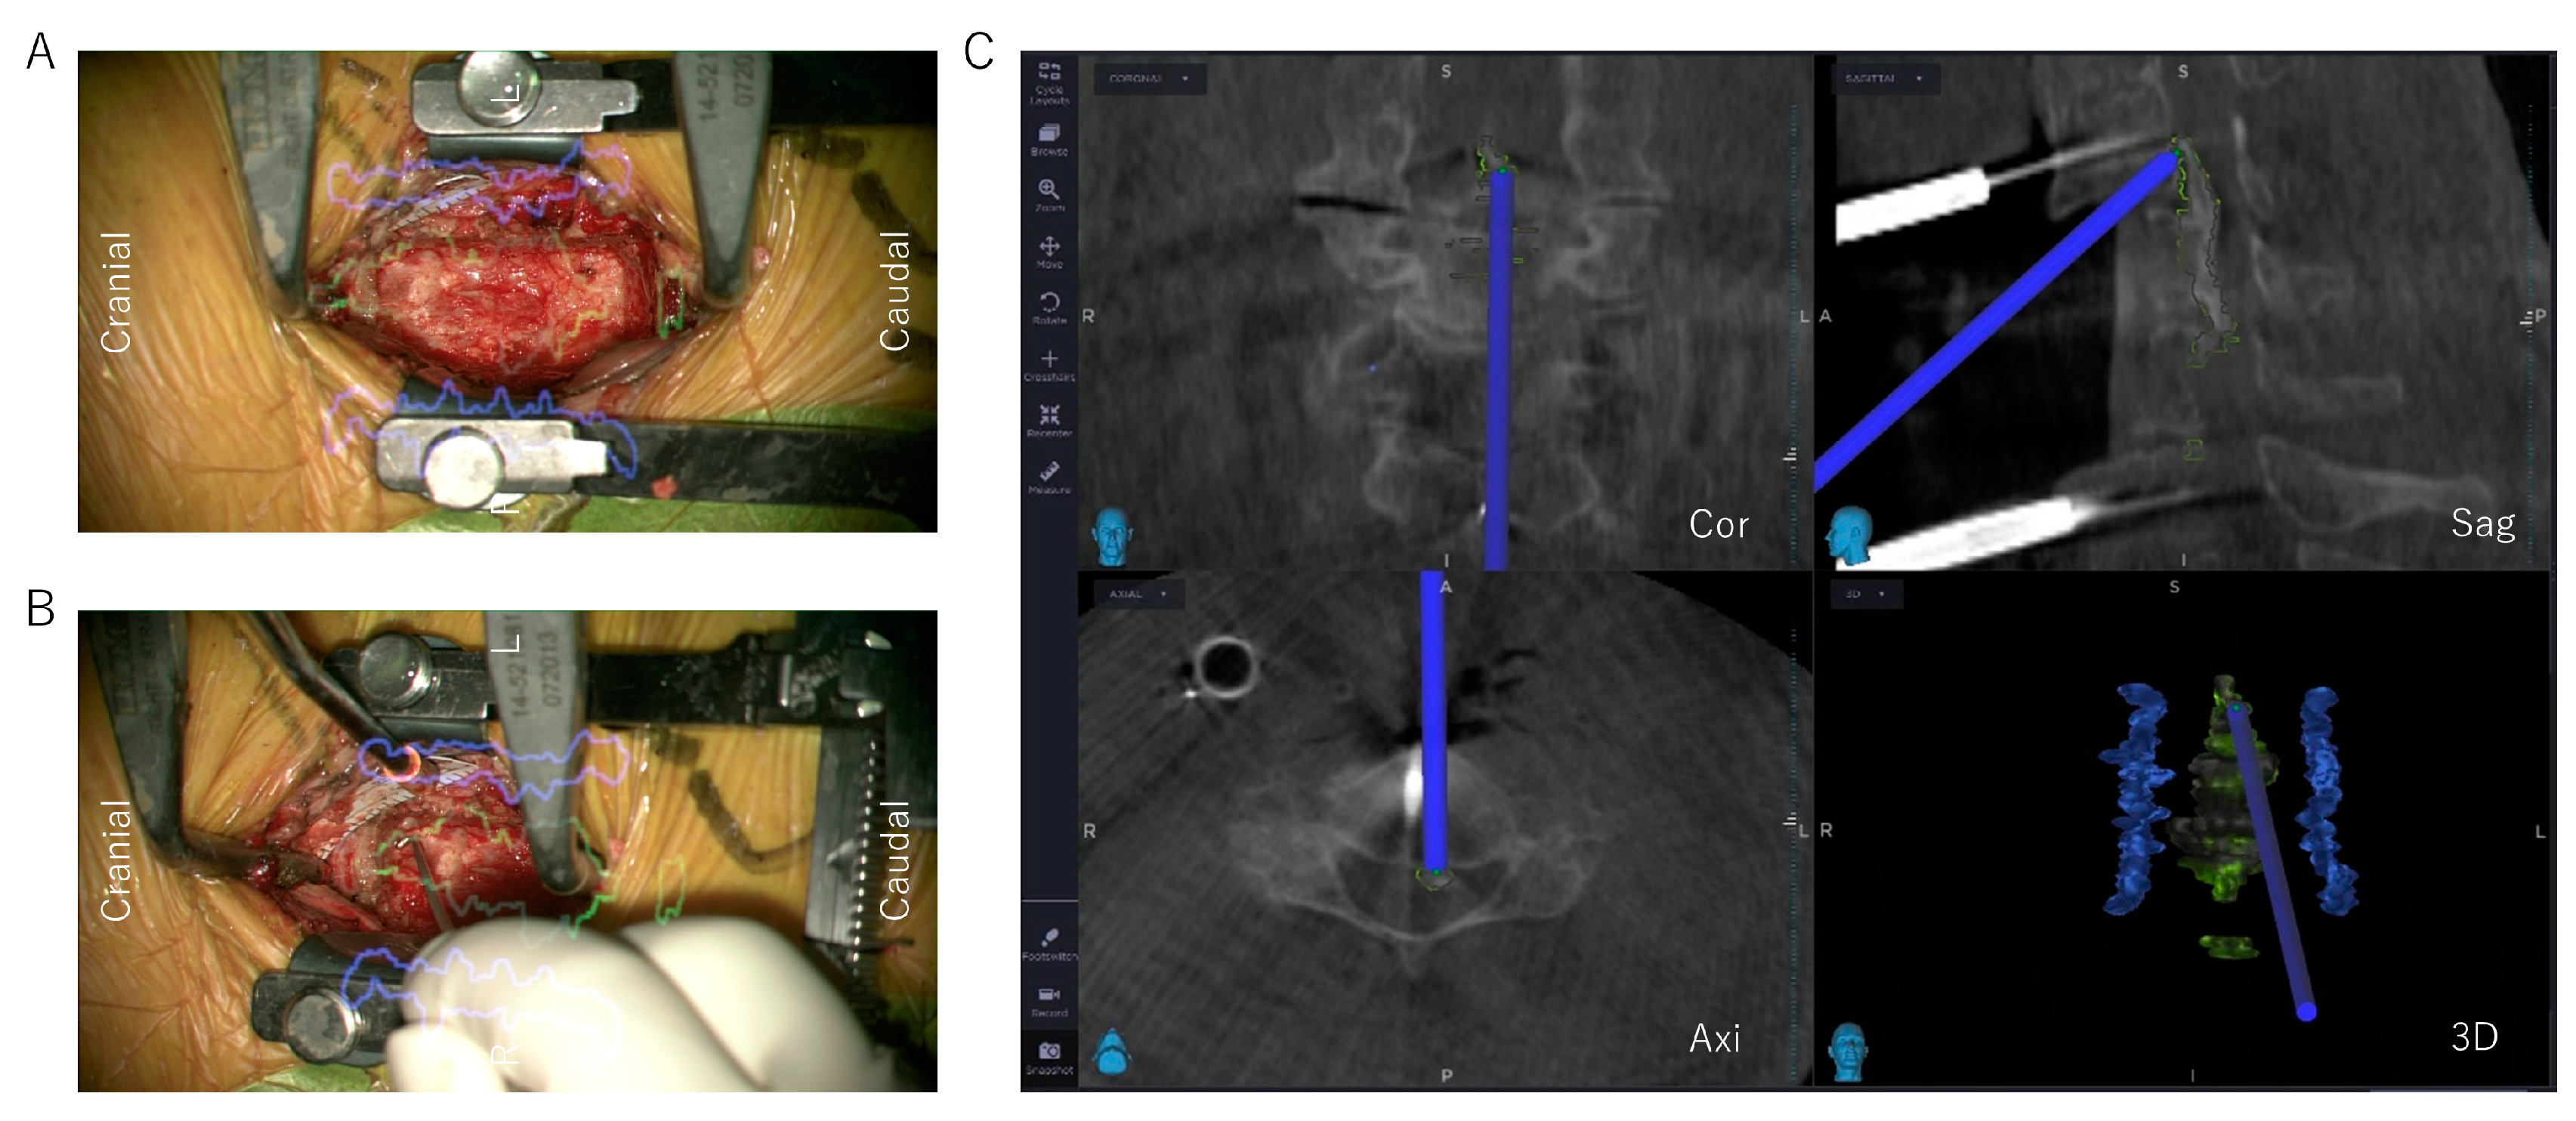

2.3. Surgical Technique of ADF with Microscopic AR Support

2.3.4. Decompression and OPLL Floating Method with Microscopic AR Support